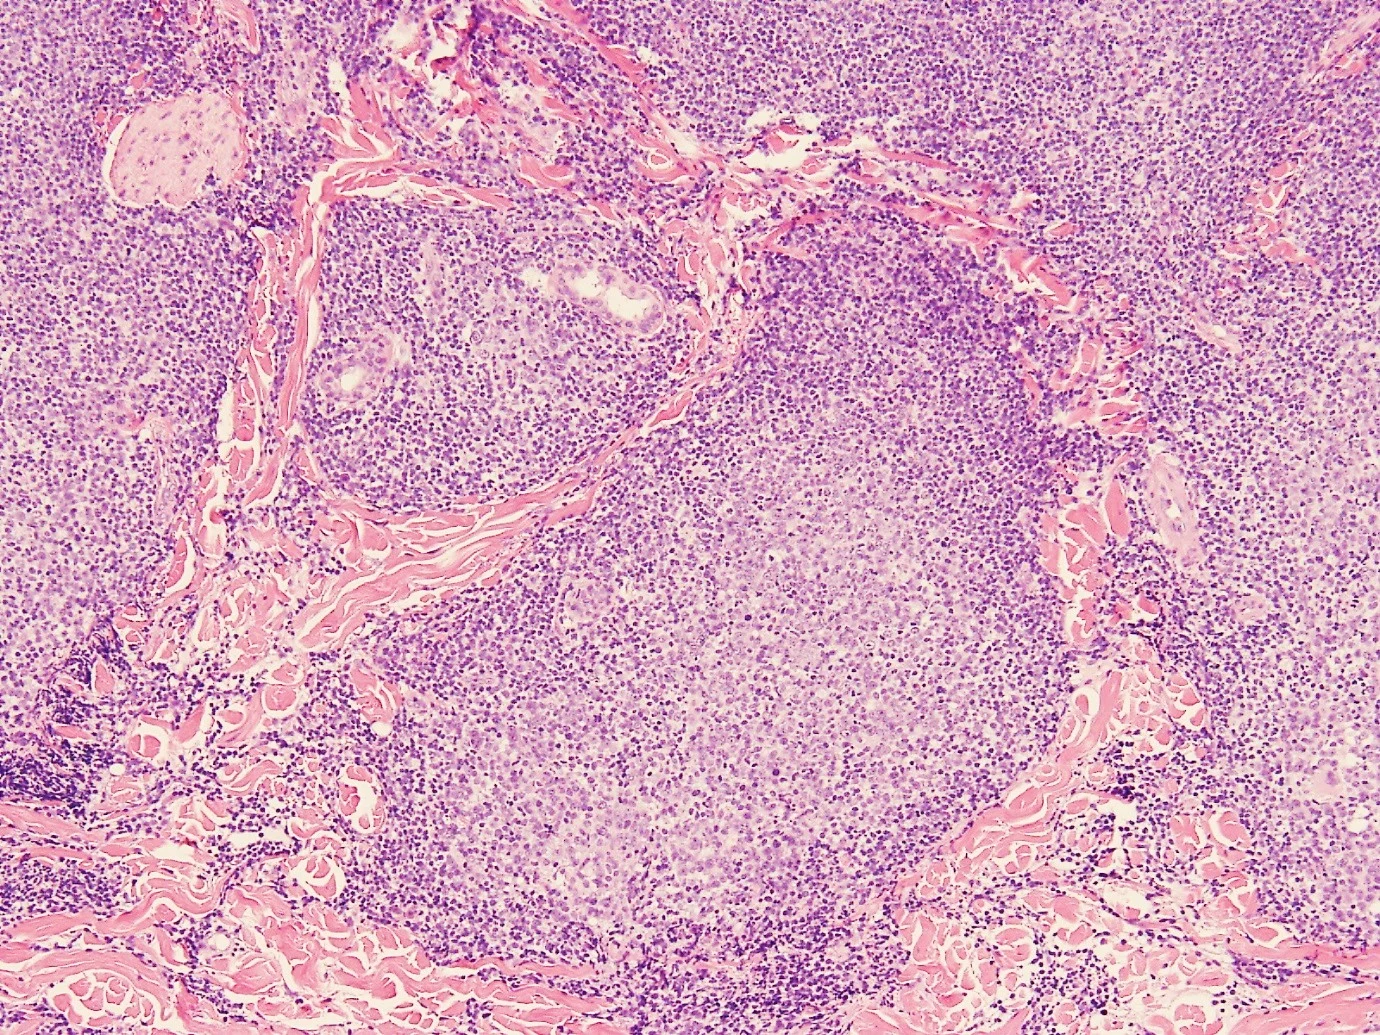

66year old male, presented with three hyperkeratotic scalp lesions, one of which is demonstrated below.

CD20

CD21

D10

BCL2

BCL6

CD79a